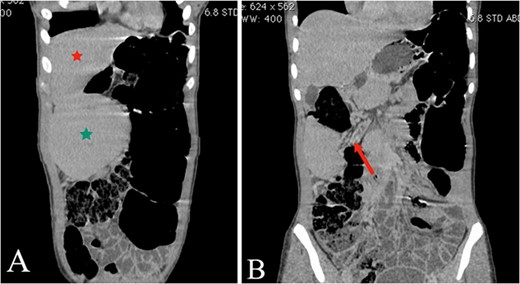

Abdominal ultrasound revealed the spleen was seen in the right lumbar region, displaying mild splenomegaly. The spleen exhibited normal texture and good vascularity. A CT scan, revealed the absence of the spleen in the left upper quadrant and confirmed the diagnosis of a WS (Figs 1 and 2). We also identified elements of splenic pedicle torsion (Fig. 1B), an associated sigmoid volvulus, and dilated tortuous short gastric vessels, indicative of left-side portal hypertension.

(A and B) The coronal plane of the abdominal CT reveals the liver (A, red star) and the WS in the right upper quadrant (A, green star), with torsion evident in the splenic mesentery (B, arrow).